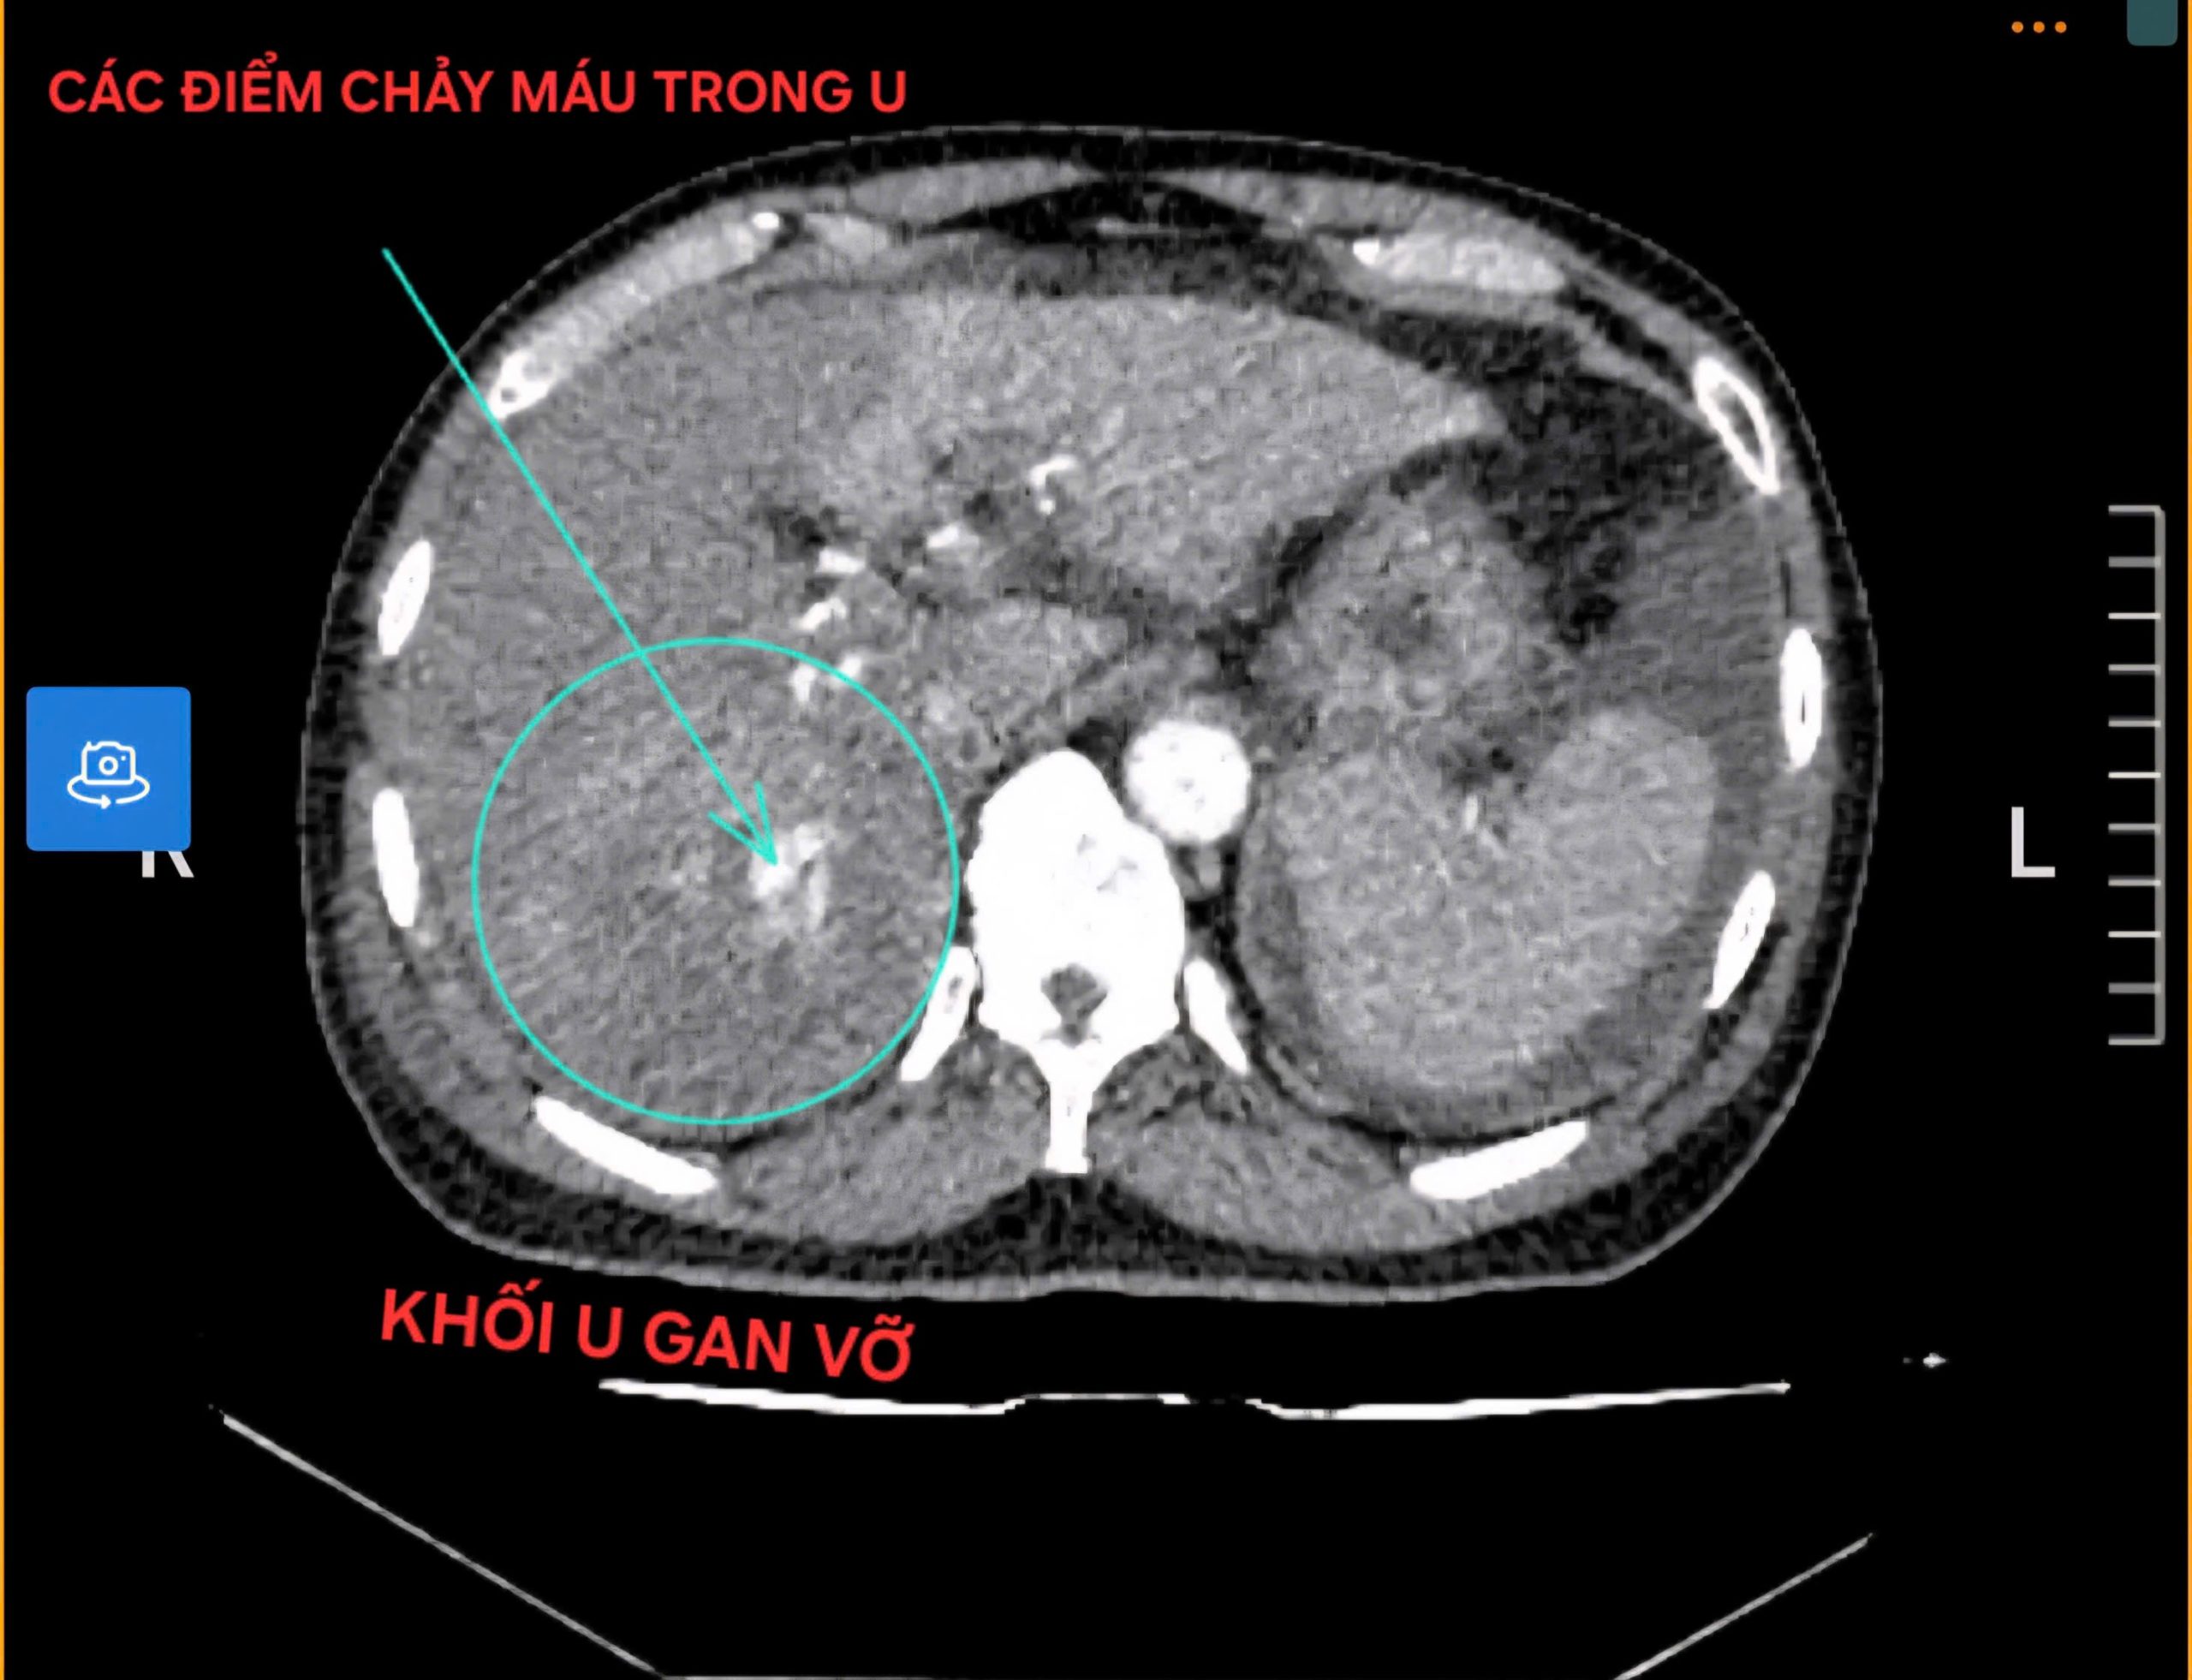

Bệnh nhân nam có tiền sử uống rượu nhiều năm, nhập viện với biểu hiện đau vùng hạ sườn phải, mạch nhanh, huyết áp tụt, dấu hiệu mất máu cấp. Kết quả Chụp cắt lớp vi tính cho thấy có khối u gan kích thước khoảng 10cm đã vỡ, gây xuất huyết ổ bụng trên nền gan xơ. Đây là biến chứng nặng của ung thư gan, có nguy cơ tử vong cao nếu không được xử trí kịp thời.

Hình ảnh trên phim chụp CLVT